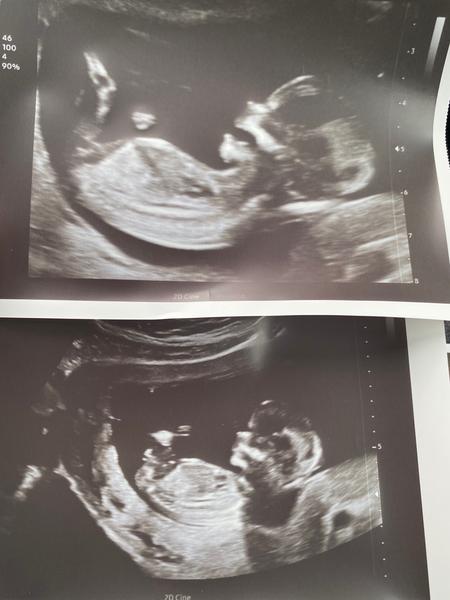

Ahoj maminky a budoucí maminky 😉 Prosím, poradila byste mi některá, co vidíte na fotce z ultrazvuku ve 20. týdnu za pohlaví? Určitě jste foteček viděly už mraky, proto vás žádám o radu...Nechci nikoho ovlivnit, proto svůj tip řeknu později 🙂 Děkuju moc!!!

@veru1999 jestli na té spodní fotečce je vidět pohlavní hrbolek a nepletu se,tak to spíše vypadá na chlapečka ♥

@charlotte28 nevim jestli se mi to zda ale dole vidím hrbolek. Vypadá to na kluka